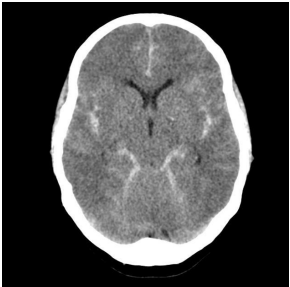

As urgências neurológicas tem importante prevalência em nosso meio. Seu diagnóstico precoce pelo médico assistente do paciente, através da tomografia, é essencial para o bom prognóstico e evolução do paciente.

https://radiopaedia.org/articles/subarachnoid-haemorrhage

Uma paciente de 23 anos trazida inconsciente, sem história de trauma, dá entrada na sala de emergência e realiza essa tomografia. Qual seria uma possível causa para a principal alteração tomográfica?